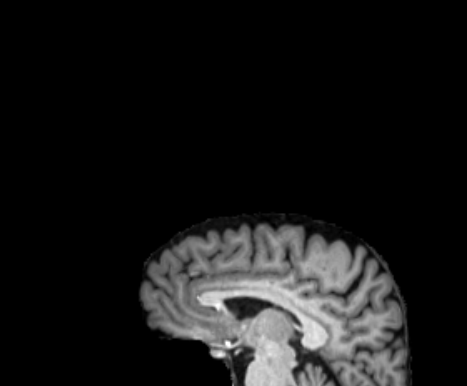

3.2.2 Robustness

In this experiment, we evaluate the robustness of Polaffini and the competing methods by computing a failure rate. We considered as potential outliers all cases for which the average Dice score over all regions after registration was below 0.34 (Z-score below -1.5, pooling Dices from all affine methods). All potential outliers were visually inspected to assess the reason behind the poor anatomical structure overlap score. All of them were clear failure cases, not just a residual misalignment to be expected after an affine registration. The failure counts for each method are reported in table 2. Almost all of the failure cases only occurred when registering with Flirt, mostly when subjects from the IXI dataset were involved. The most common failure type, showcased in Fig 6-a., consists of a local minimum where the frontal part of the moving brain is matched with the cerebellum of the reference one, a less frequent upside-down outcome is showcased in Fig 6-b. We suspect it is due to the fact that images from IXI have their axes ordered differently compared to the other two datasets and the template. However, since this information is contained in the header, it is unclear why Flirt could not handle the situation properly. Without the restriction of the angle search to , Flirt would give worse results (19 failure cases for subject-to-template and 61 for subject-to-subject). The only failure case using Anima for subject-to-subject is shown in Fig 6-c. For the rest of this section, we discard registrations if at least one of the methods has failed.

| reference | moving | moved | reference and moved | |

| a. | ukb_1154012-20252 | adni_AD-012-S-0720 | registered with Flirt | |

![]() |

|

| b. | ixi_165-HH-1589 | ukb_1145033-20252 | registered with Flirt | |

| c. | ixi_143-Guys-0785 | adni_MCI-003-S-6258 | registered with Anima-aff | |